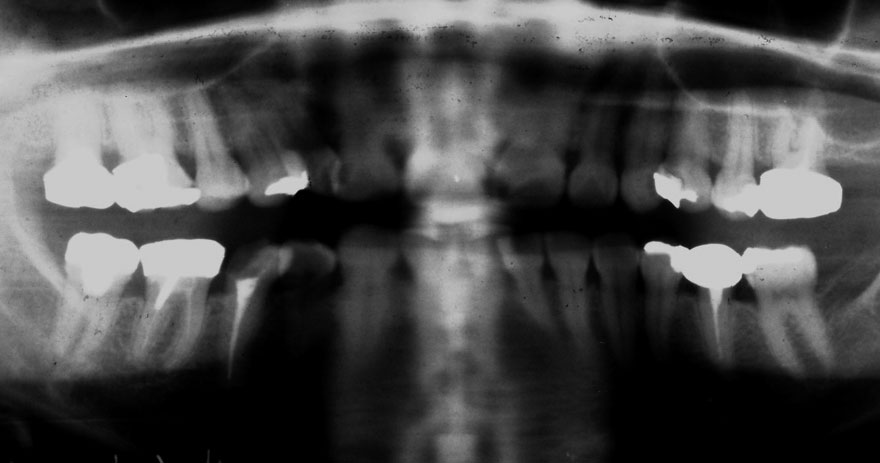

開始年齢 40代

初診時 40歳 女性 平均歯槽骨喪失量:3.14mm

32年後 72歳

平均歯槽骨喪失量:3.22mm

32年間喪失量:-0.08mm

年間喪失速度:-0.002mm

(ケア頻度:1.86ヵ月ごと)